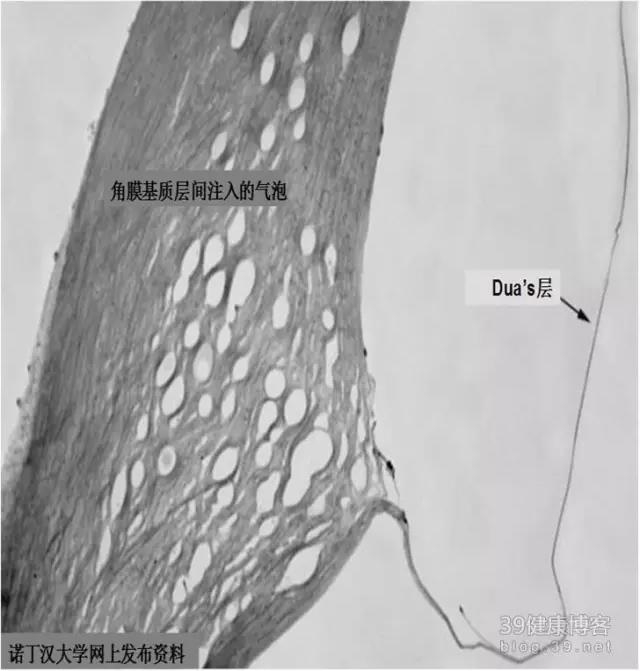

新发现的角膜Dua’s层

Dua等在后弹力膜前发现了一层以前没有检测到的角膜无细胞组织层,厚度约15?m。

其解剖位置在角膜基质与后弹力膜之间。尽管这一层膜很薄,但很坚强、而且不透空气。足以承受高达200 kPa的压力。Dua等认为在实施深板层移植剖切板层的过程中,如果能将气泡注入Dua层之下,将有可能减少后弹力膜撕裂的风险。他还猜测,圆锥角膜造成的突发性角膜水肿,可能是该层组织撕裂造成的结果。